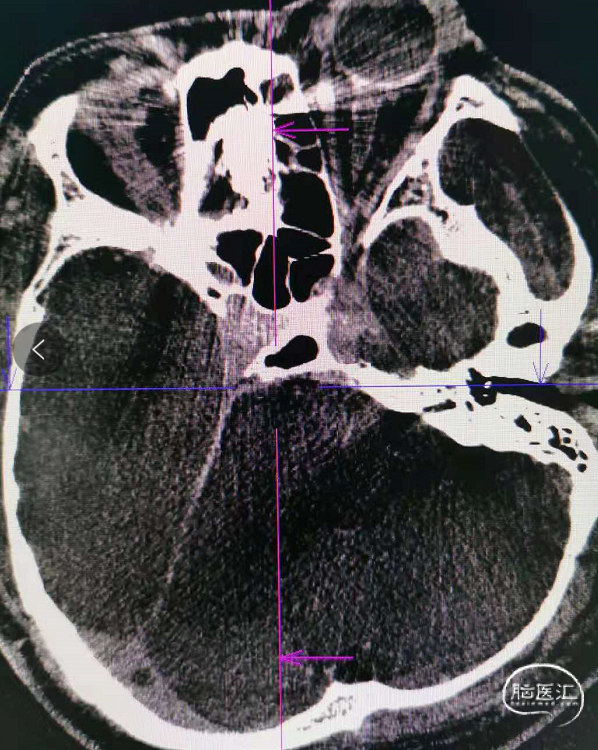

治疗经过